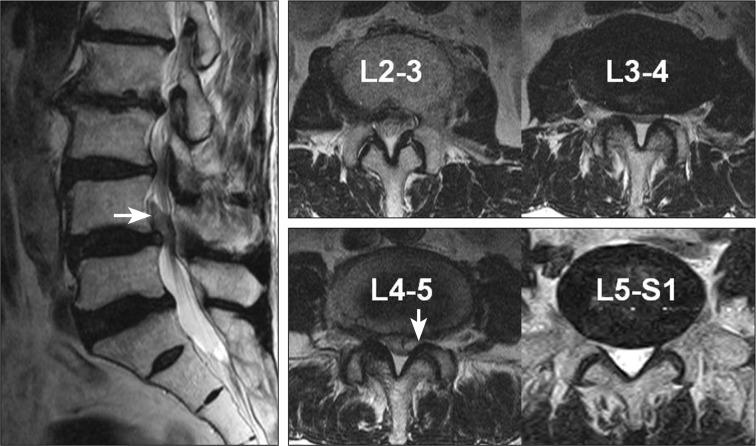

The authors report 2 cases of nerve root herniation after discectomy of a large lumbar disc herniation caused by an unrecognized dural tear. Patients complained of the abrupt onset of radiating pain after lumbar discectomy. Magnetic resonance imaging showed cerebrospinal fluid signal in the disc space and nerve root displacement into the disc space. Symptoms improved after the herniated nerve root was repositioned. Clinical symptoms and suggestive radiologic image findings are important for early diagnosis and treatment.

作者报告了2例因未识别的硬脊膜撕裂导致大的腰椎间盘突出症行椎间盘切除术后神经根疝的病例。患者在腰椎间盘切除术后出现突发的放射性疼痛。磁共振成像显示椎间盘间隙有脑脊液信号,神经根移位至椎间盘间隙。将疝出的神经根复位后症状改善。临床症状和提示性的影像学表现对早期诊断和治疗很重要。